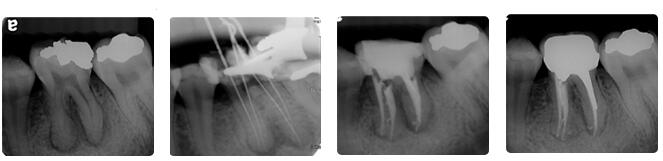

根管治疗通常包括三个基本步骤:根管预备、根管消毒、根管充填。

首先会清除根管内的炎症牙髓和坏死物质,接下来测量根管长度,并适当扩大根管(即根管预备过程),然后在根管内封药消毒,较 后用药物充填根管。

根管治疗时,拍牙片是很有必要的,并且至少要保证3张牙片。

第一张在治疗前,帮助医生了解牙根的基本情况,制定治疗计划;

第二张在治疗中,帮助医生了解治疗情况,如根管预备是否到位等,并制定下一步治疗方案;

第三张是在治疗结束后,帮助判定根管充填质量,发现问题及时补救。